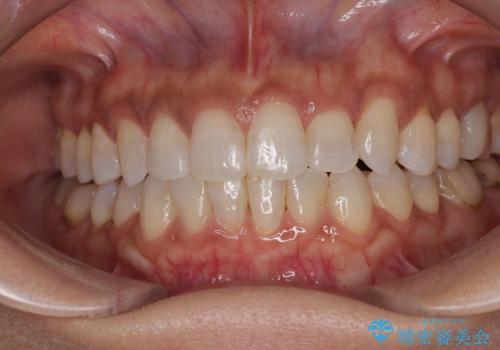

捻れて前に出ている前歯 ワイヤー装置での非抜歯矯正